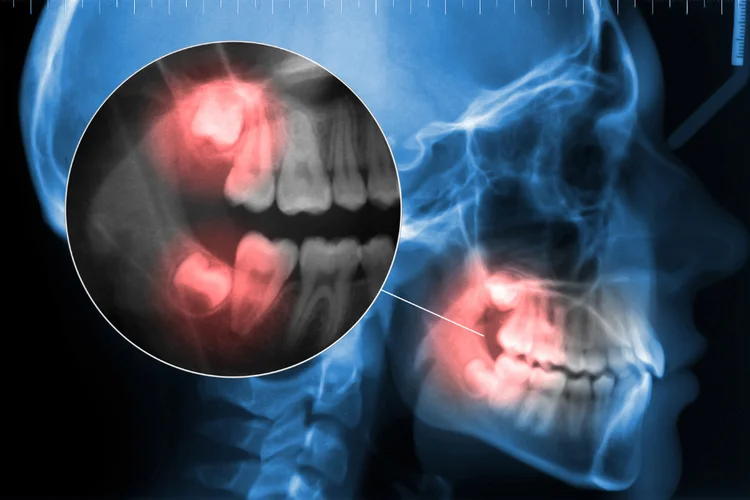

- Impaction – A wisdom tooth that is partially or fully trapped in the jawbone or gums, often leading to pain, swelling, and potential infection due to difficulty in eruption.

- Pericoronitis – Inflammation of the gum tissue around a partially erupted wisdom tooth, often leading to tenderness, swelling, and infection due to bacterial buildup.

- Pressure on Gum Tissues – As a wisdom tooth emerges, it may press against the surrounding gum tissues and cause inflammation. Occasionally, the erupting wisdom tooth on the upper jaw may press on the lower gums and cause ulcerations as well.

- Tooth Decay – Impacted wisdom teeth are harder to clean due to their position, allowing plaque buildup that increases the risk of cavities and further discomfort.

- Infection – Bacteria build up around an emerging wisdom tooth due to trapped food and difficulty in cleaning, leading to swelling, pain, and pus formation.